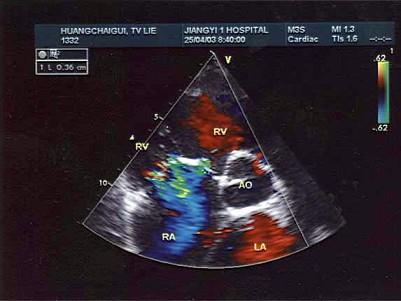

问题 某患者收缩期三尖瓣口超声心动图如图所示,提示?(?)

选项 A.三尖瓣狭窄 B.三尖瓣关闭不全 C.房间隔缺损 D.正常声像图 E.室间隔缺损

答案 B